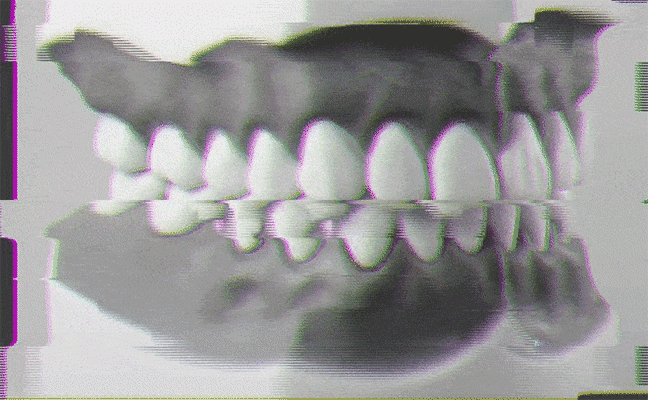

Para ello, ante los primeros síntomas ya descritos, desde el Colegio de Odontología se recomienda pasar por un especialista para realizar una valoración completa antes de autodiagnosticarse. «Esto incluye una historia clínica con preguntas sobre salud dental general, medicación actual y hábitos de sueño, entre otros campos de interés. Debe complementarse con una exploración bucodental, buscando signos de desgaste, así como la posible presencia de dolor en la musculatura mandibular o ruidos en la articulación. Este estudio muchas veces se complementa con una toma de impresiones, análisis de los modelos y radiografías», detalla el citado especialista.